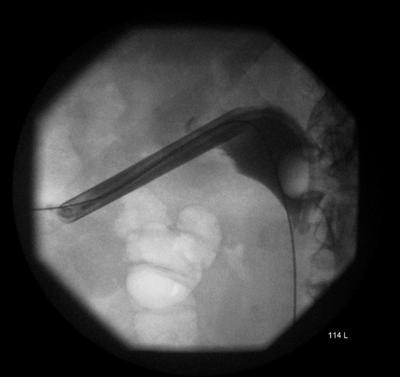

Figure 3.

The lower ureter was tortuous and of the ‘fish-hook’ type. A nephrostogram revealed a stricture at the vesicoureteric junction (VUJ) and incision of the VUJ using a Collins knife failed to demonstrate the lumen (Figure 2 and 3).